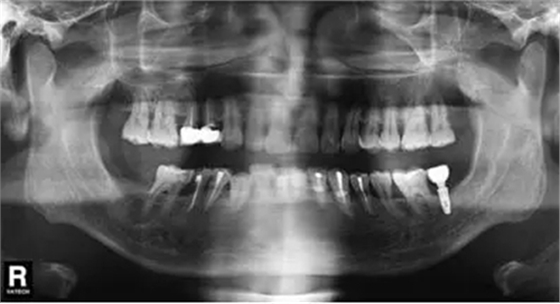

圖9 拔除47植入骨粉膠原塞曲面體層片

微創(chuàng)拔除47后,植入骨粉膠原塞(圖7~9);3個月后CBCT分析骨質;行47種植牙修復術。